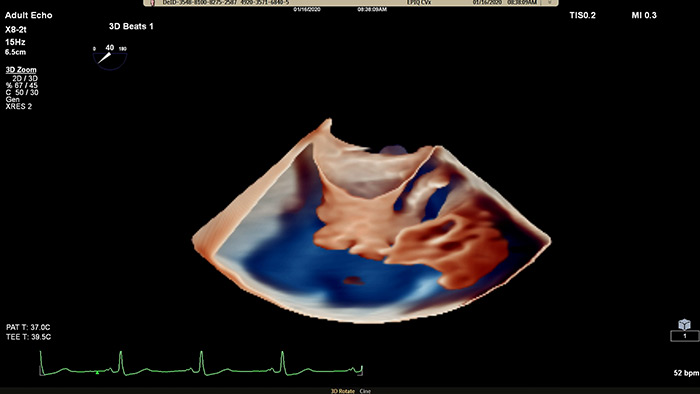

Visualize cardiac morphology using ultrasound with TrueVue Glass